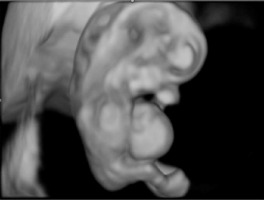

A thirty-three-year-old pregnant woman in her second pregnancy (the first pregnancy was unsuccessful – miscarriage at week 8 of pregnancy), visited a gynecologist for a routine check-up at week 12 of pregnancy, during which developmental disorders were found in the anterior chest cavity and abdominal walls. The woman was healthy, denied having chronic diseases, and was taking folic acid and vitamin preparations for pregnant women. The patient also denied the existence of any infections at an early stage of pregnancy. The woman was referred to the Laboratory of Prenatal Research, where, during prenatal ultrasound examination, the fetus was diagnosed with a complex defect of the skin and division of the body’s cavities in the form of pentalogy of Cantrell. The fetus was diagnosed with umbilical cord omphalocele (Figure 1), diaphragmatic hernia with diaphragmatic defect, sternal defect, ectopic heart and pericardial defect (Figures 2-3).

Moreover, the fetal heart seemed to possess four cavities, two slightly asymmetrical inflows of the ventricles and the origins of two vessels in abnormal relationships were visualized (Figures 4-5).